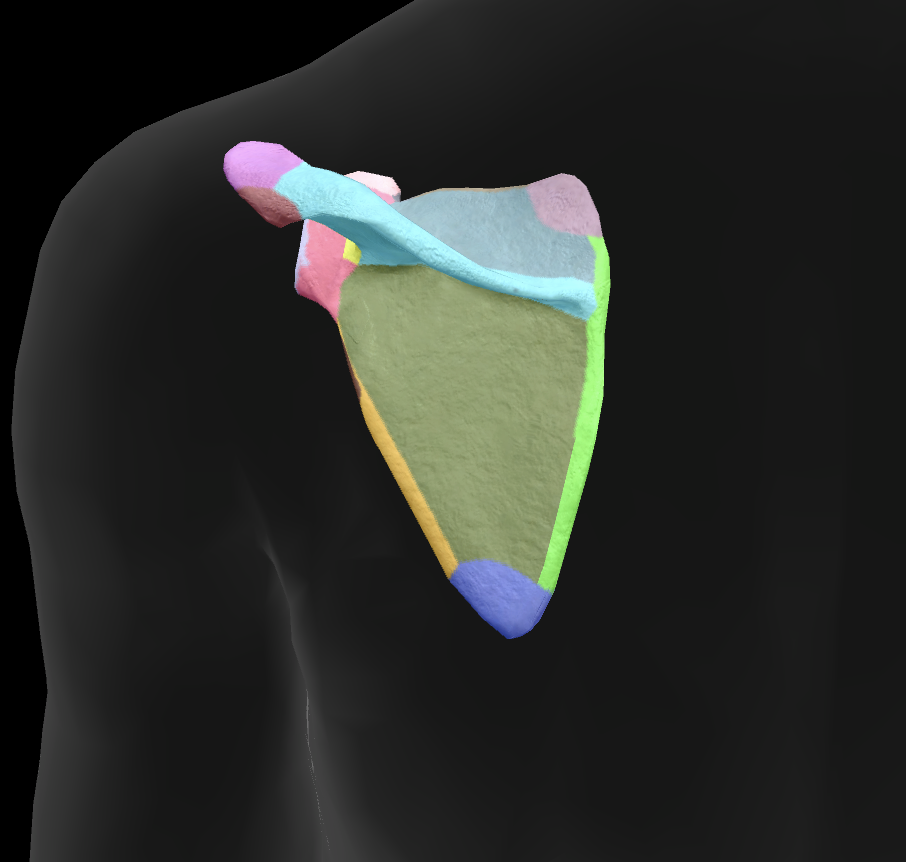

scapula

What is this boney landmark?

spine of scapula

What is this boney landmark?

supraspinous fossa

What is this boney landmark?

infraspinous fossa

What is this boney landmark?

acromion process

What is this boney landmark?

superior angle

What is this boney landmark?

inferior angle

What is this boney landmark?

lateral border

What is this boney landmark?

medial border

What is this boney landmark?

subscapular fossa

What is this boney landmark?

spinoglenoid notch

What is this boney landmark?

glenoid fossa

What is this boney landmark?

supraglenoid tubercle

What is this boney landmark?

infraglenoid tubercle

What is this boney landmark?

coracoid process